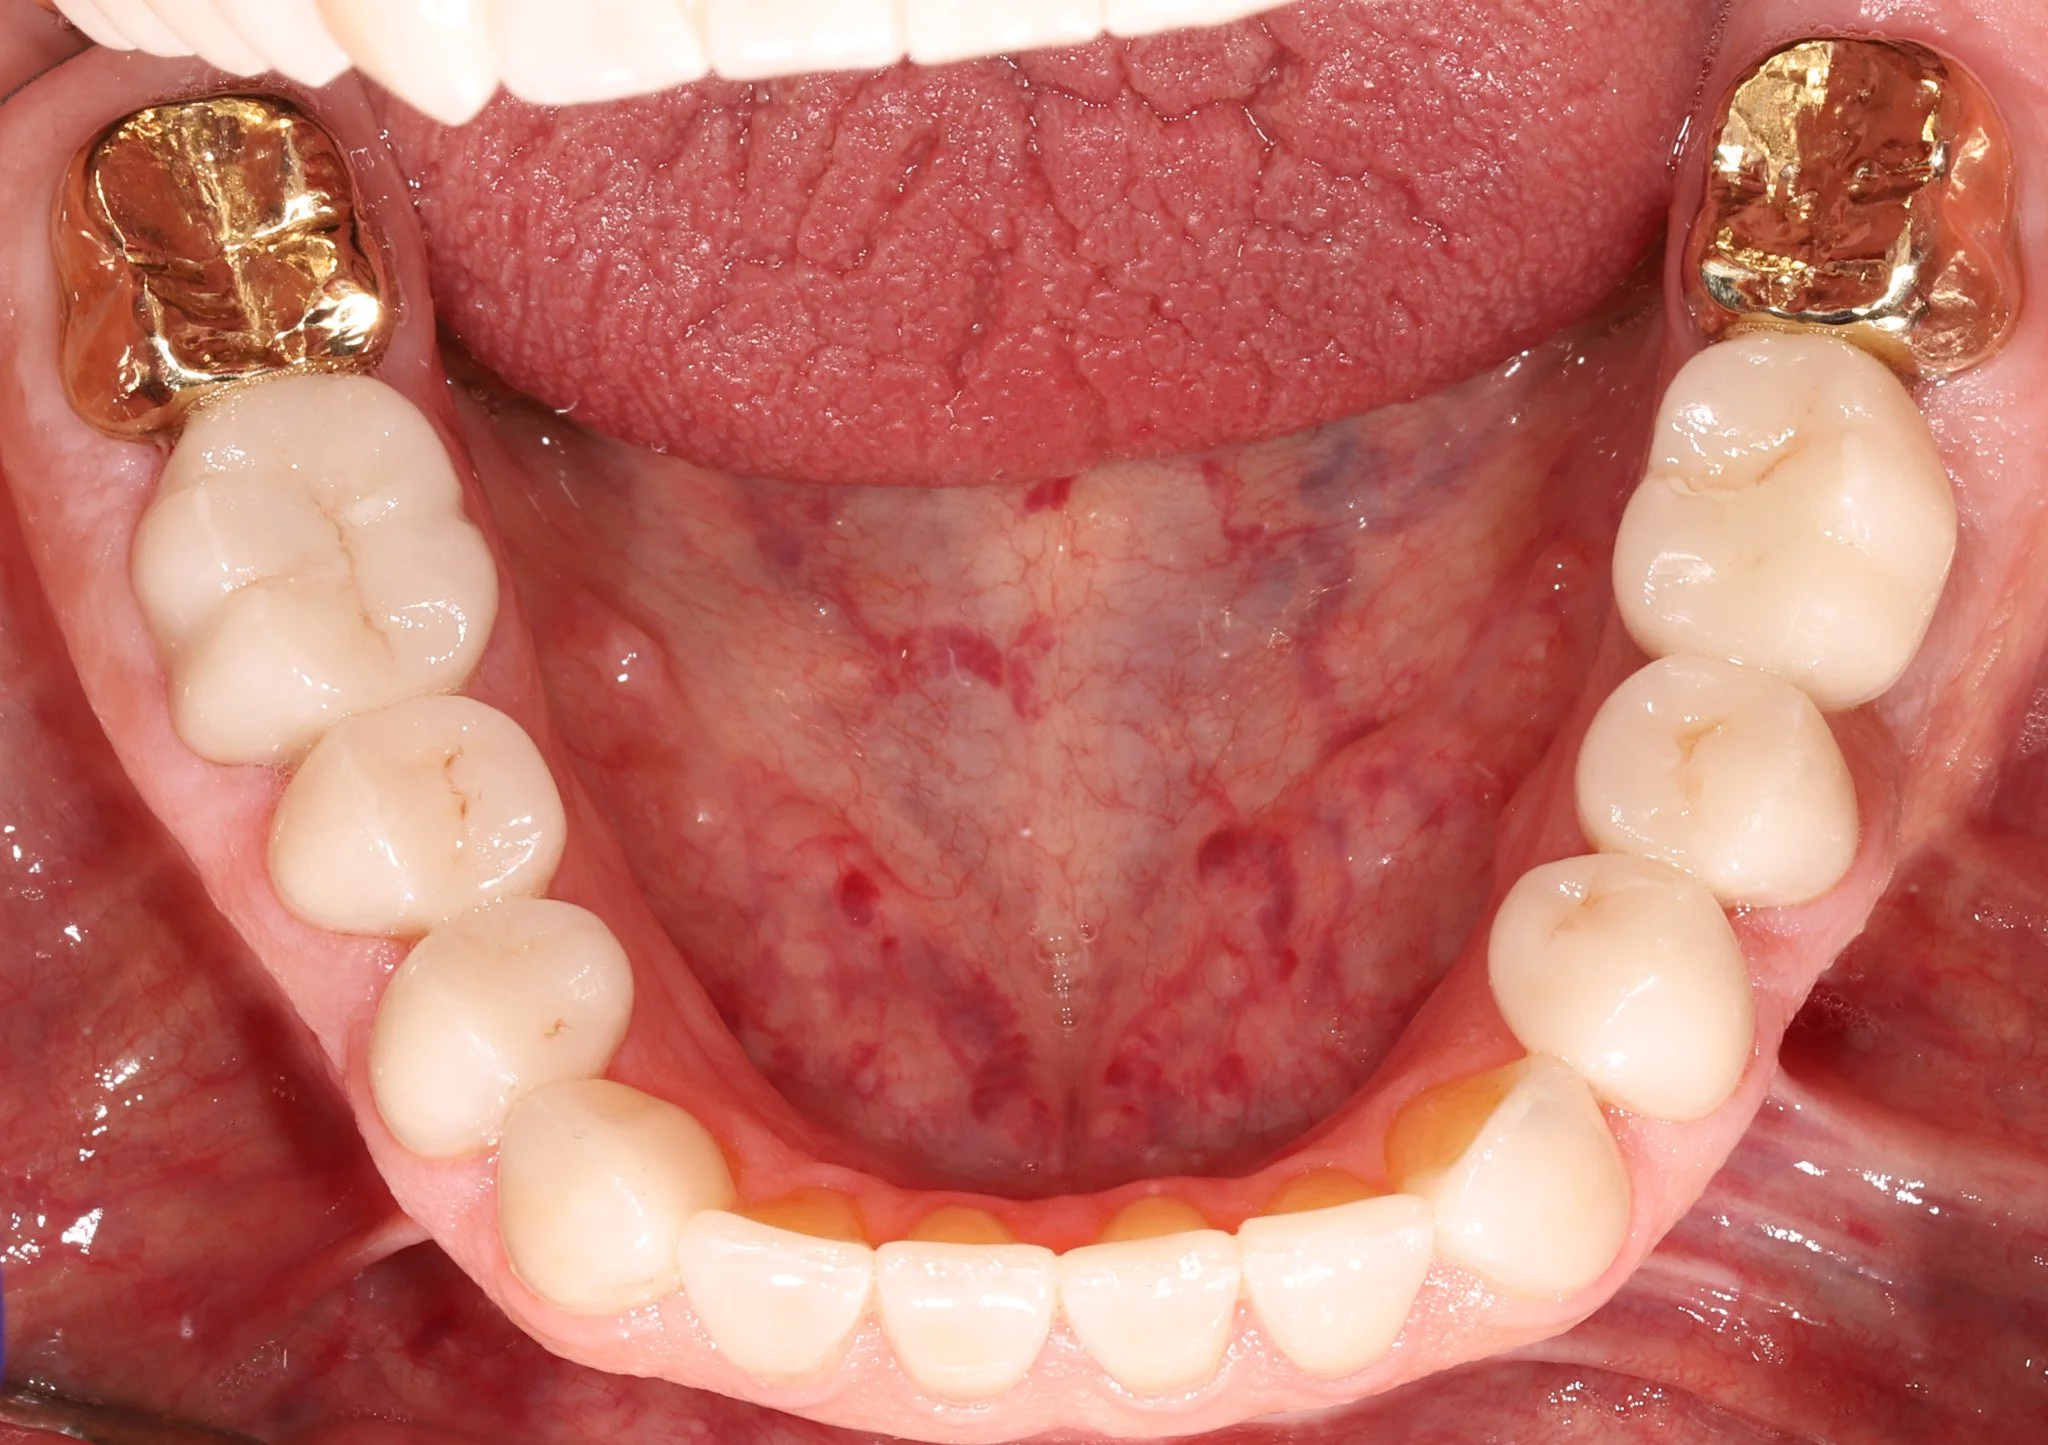

Close-up of the lower teeth showing decay and acid erosion.  Prior to restorative treatment.

Before: Back 2 teeth each side have decay, acid erosion, wear

Close-up of the restored teeth with bonded porcelain crowns that fit and blend with natural dentition.

After: Bonded porcelain restorations to seal and protect teeth while adding back missing structure